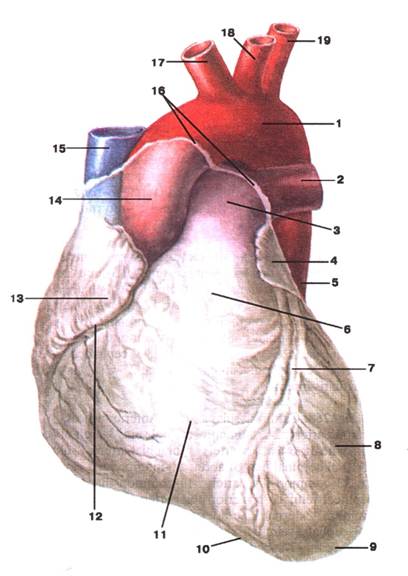

Малюнок А. 7 – Cor. Вигляд спереду. Перикард видалений:

1 -arcus aortae; 2 -а. pulmonalis sinistra; 3 -truncus pulmonalis; 4 -auricula sinistra; 5 -pars descendens aortae; 6 -conus arteriosus; 7 -sulcus interventric‑ularis anterior; 8 -ventriculus sinister; 9 -apex cordis; 10 -incisura apicis cordis; 11 -ventriculus dexter; 12 -sulcus coronarius; 13 -auricula dextra; 14 -pars ascendens aortae; 15 -v. cava supeior; 16 -переход pericardium в epicardium; 17 -truncus brachiocephalicus; 18 -a. carotis communis sinistra; 19 -a. subclavia sinistra